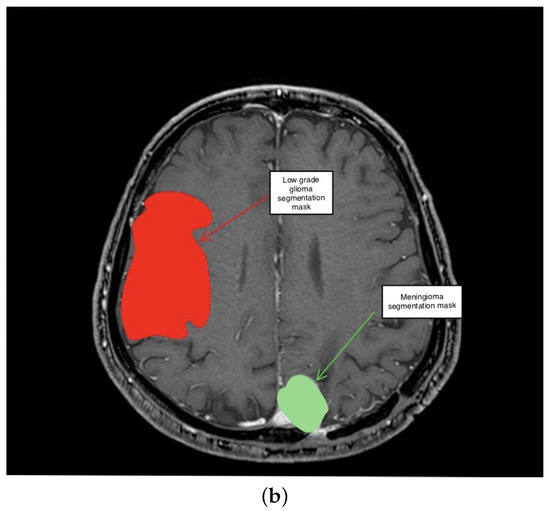

3.2. Second Scenario